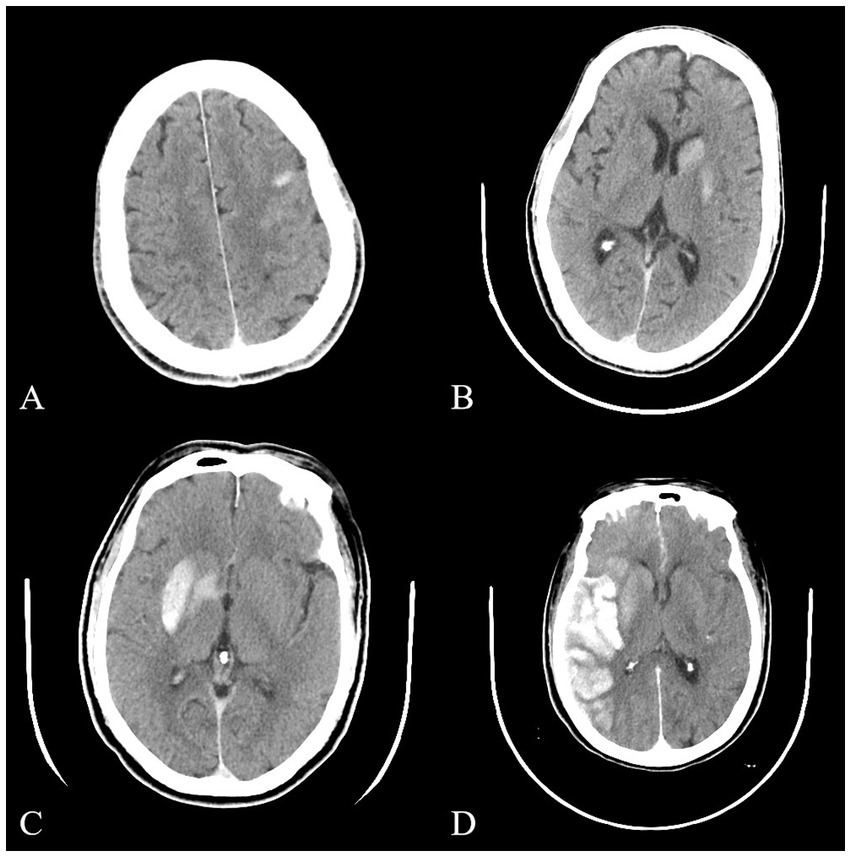

Objective: To explore the risk factors, classification, relation with hemorrhage and clinical significance of high-density shadow on immediate cerebral CT in patients with large vessel occlusion acute ischemic stroke after successful interventional recanalization. Methods: A retrospective analysis was conducted on patients with acute ischemic stroke due to anterior circulation large vessel occlusion who received interventional recanalization from January 2019 to December 2023 in Heyuan People's Hospital. The main inclusion criteria included NIHSS score ≥6 points at the time of onset, The time from onset to femoral artery puncture ≤24 hours and so on. The main exclusion criteria included pre onset mRS score > 2 points, the vital signs were unstable during the onset of the disease and so on. Variables we studied included NIHSS score at admission, preoperative ASPECT score, blood flow reperfusion eTICI grading, surgical methods and so on. According to the distribution, density, volume, etc. of cerebral hyperdensity, high-density shadow was divided into cortical type, soft type, metallic type, and diffuse type. Results: 318 patients showed high-density shadow on cerebral CT immediately after successful interventional recanalization. In multiple logistic regression analysis, the history of hypertension and preoperative ASPECT score were correlated independently with the occurrence of high-density shadow. 27 patients experienced symptomatic intracranial hemorrhage. It was found that high-density shadow was not independent with symptomatic intracranial hemorrhage in univariate logistic regression analysis (P>0.05). In the classification of high-density shadow, there were 16 cases of cortical type, 85 cases of soft type, 80 cases of metallic type, and 137 cases of diffuse type. Patients with diffuse type had the highest incidence of futile recanalization, symptomatic intracranial hemorrhage, malignant brain edema, and highest mortality rate within 3 months after surgery (P<0.05). Conclusion: A low preoperative ASPECT score was an independent risk factor of high-density shadow on immediate cerebral CT after successful interventional recanalization, while a history of hypertension, mere use of balloon angioplasty and combination of balloon angioplasty and stent implantation may serve as a protective factor. Patients with diffuse high-density shadow had the worst prognosis and the highest incidence of symptomatic intracranial hemorrhage and malignant brain edema.